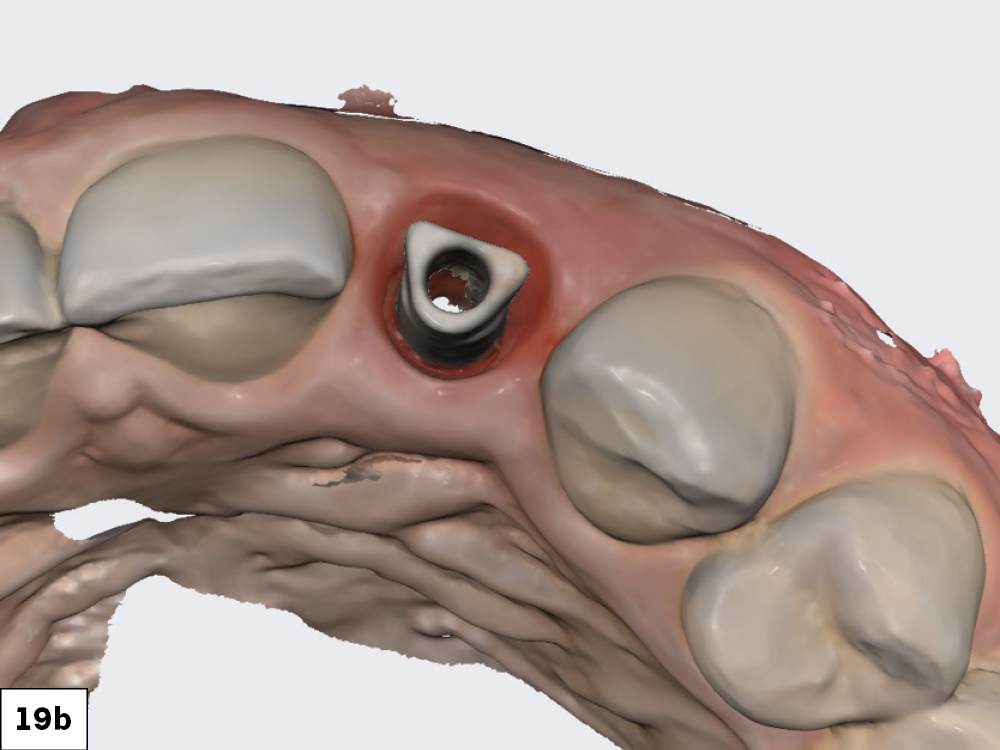

Figures 19a, 19b: The scan body was then registered with the IOS. With the soft tissue previously scanned and locked in place, there was no concern about the soft tissue collapsing while the scan body was being radiographed and its position captured.

As determined from the digital treatment plan prior to extraction and implant placement, a custom hybrid abutment and a cement-retained BruxZir® Esthetic crown were fabricated.